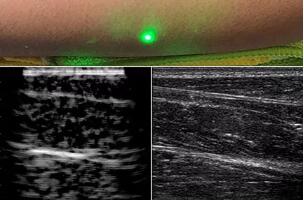

臨床應用的無(wú)創(chuàng )超聲,要求探頭與人體皮膚直接接觸來(lái)向身體傳導高頻振動(dòng)的超聲波。但是,有一些特定的患者卻在超聲檢查時(shí)受到限制,比如兒童、燒傷患者和敏感皮膚患者等。而近日麻省理工學(xué)院的研究人員證明,確實(shí)有可能使用激光在不接觸皮膚的前提下對患者進(jìn)行超聲波掃描。

而麻省理工學(xué)院的研究小組現在開(kāi)發(fā)了一種使用激光檢測皮膚上超聲波振動(dòng)的方法,以便可以使用一種激光使皮膚產(chǎn)生共振,而另一種則可以檢測到振動(dòng),從而達到“遠程超聲掃描”的作用。

目前,研究人員已經(jīng)與健康的志愿者測試了他們的系統:從半米遠處掃描了他們的前臂,并將這些結果與傳統超聲的結果進(jìn)行了比較。他們能夠觀(guān)察到深達6厘米的組織,并能看到肌肉,脂肪和骨頭,并報告其結果可與標準超聲相媲美。

研究人員用一種激光裝置測試了這個(gè)想法,該裝置使用一個(gè)波長(cháng)為1,550納米的脈沖激光來(lái)產(chǎn)生聲波,并使用第二個(gè)連續激光,調諧到相同的波長(cháng)以遠程檢測反射的聲波。第二個(gè)激光器是靈敏的運動(dòng)檢測器,可測量聲波從肌肉,脂肪和其他組織反射回來(lái)而引起的皮膚表面振動(dòng)。反射的聲波產(chǎn)生的皮膚表面運動(dòng)會(huì )導致激光頻率發(fā)生變化,這種變化可以測量。通過(guò)機械掃描人體上的激光,科學(xué)家可以獲取不同位置的數據并生成該區域的圖像。